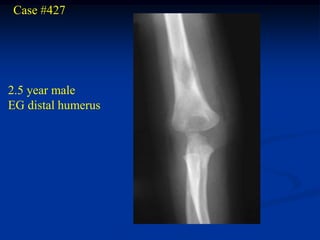

Case #427

2.5 year male

EG distal humerus

Lateral view